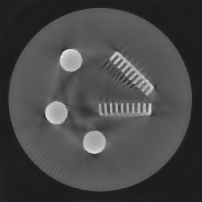

Figure 4. Results of different methods for reconstructing the gel phantom with underdetermined rate 77%. (a) FBP, (b) L2-TV with scalar λ𝜆\lambda, (c) Our method, (d) λ𝜆\lambda in our method.

Example 2. Additionally to the simulated data, we also test our method on real CT measurements. In this experiment the gel phantom shown in Figure 1 (b) is measured using a fan-beam geometry with 560 beams and 360 or 180 projection angles. The reconstructions are in a square domain of 512×\times512 pixels, which result in an under-determined rate of 77% and of 38%, respectively.

In Figure 4 and 5 we compare our method with the FBP algorithm and the L2-TV method. Due to insufficient measurements and noise, FBP cannot provide satisfactory results. Comparing the results obtained by our method with the ones from the L2-TV method, we see that our method reduces more artifacts while keeping similar quality on reconstructed object textures. Furthermore, from the final values of λ𝜆\lambda obtained in our method we find that our method can correctly distinguish textured regions from homogeneous regions. Then, by setting different regularization parameter values, we vary the strength of the smoothness in the different regions.